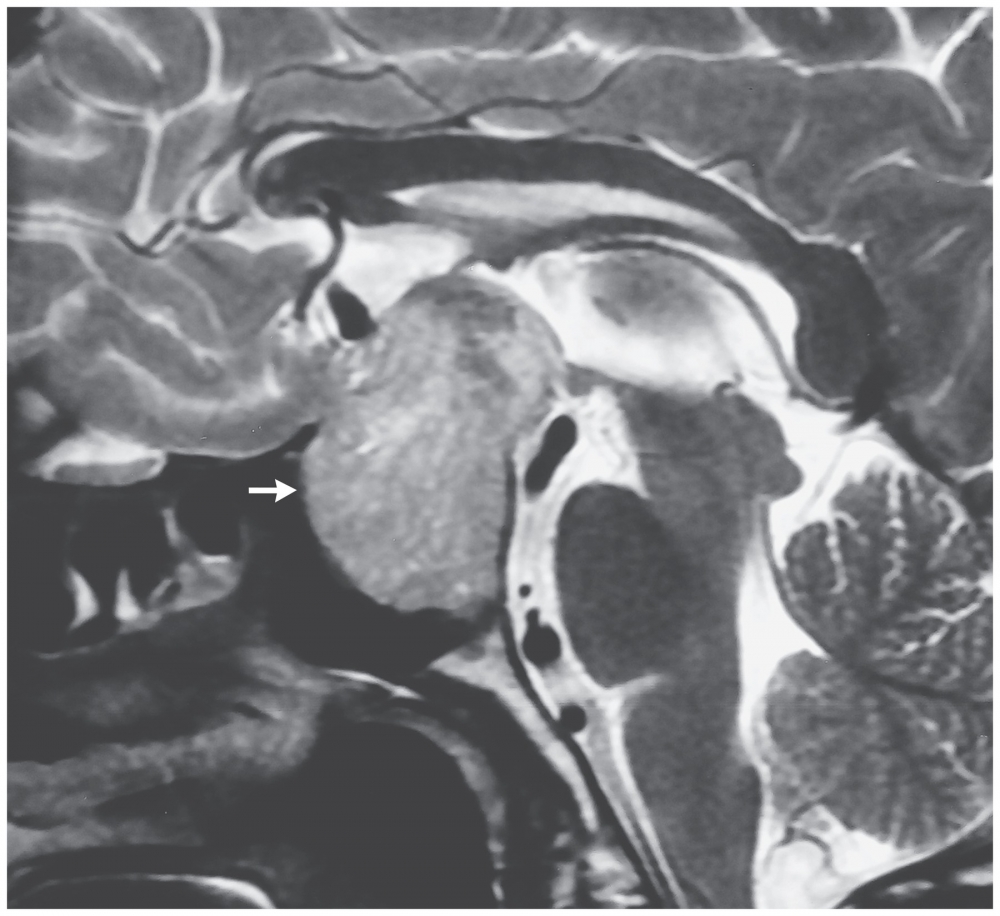

The pendular form usually arises from a midline, extrinsic, suprasellar mass lesion compressing or invading the brainstem bilaterally at the junction of the midbrain and diencephalon2.